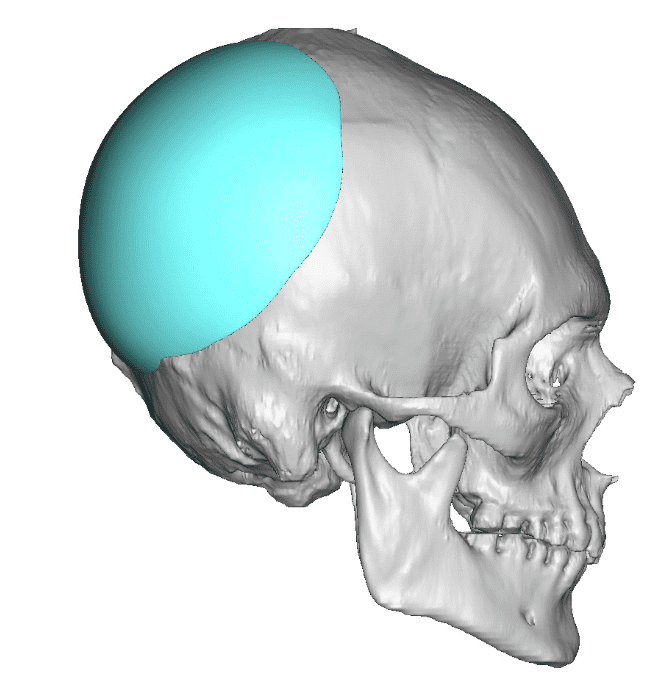

Desire for an improved head shape so that it looks rounder and not so peaked or sloped.

Placement of custom skull implant for parasagittal augmentation to create a rounder head shape. An example of what appears to be a high sagittal crest that is really low parasagittal skull areas.

Desire for an improved head shape so that it looks rounder and not so peaked or sloped.

Placement of custom skull implant for parasagittal augmentation to create a rounder head shape. An example of what appears to be a high sagittal crest that is really low parasagittal skull areas.